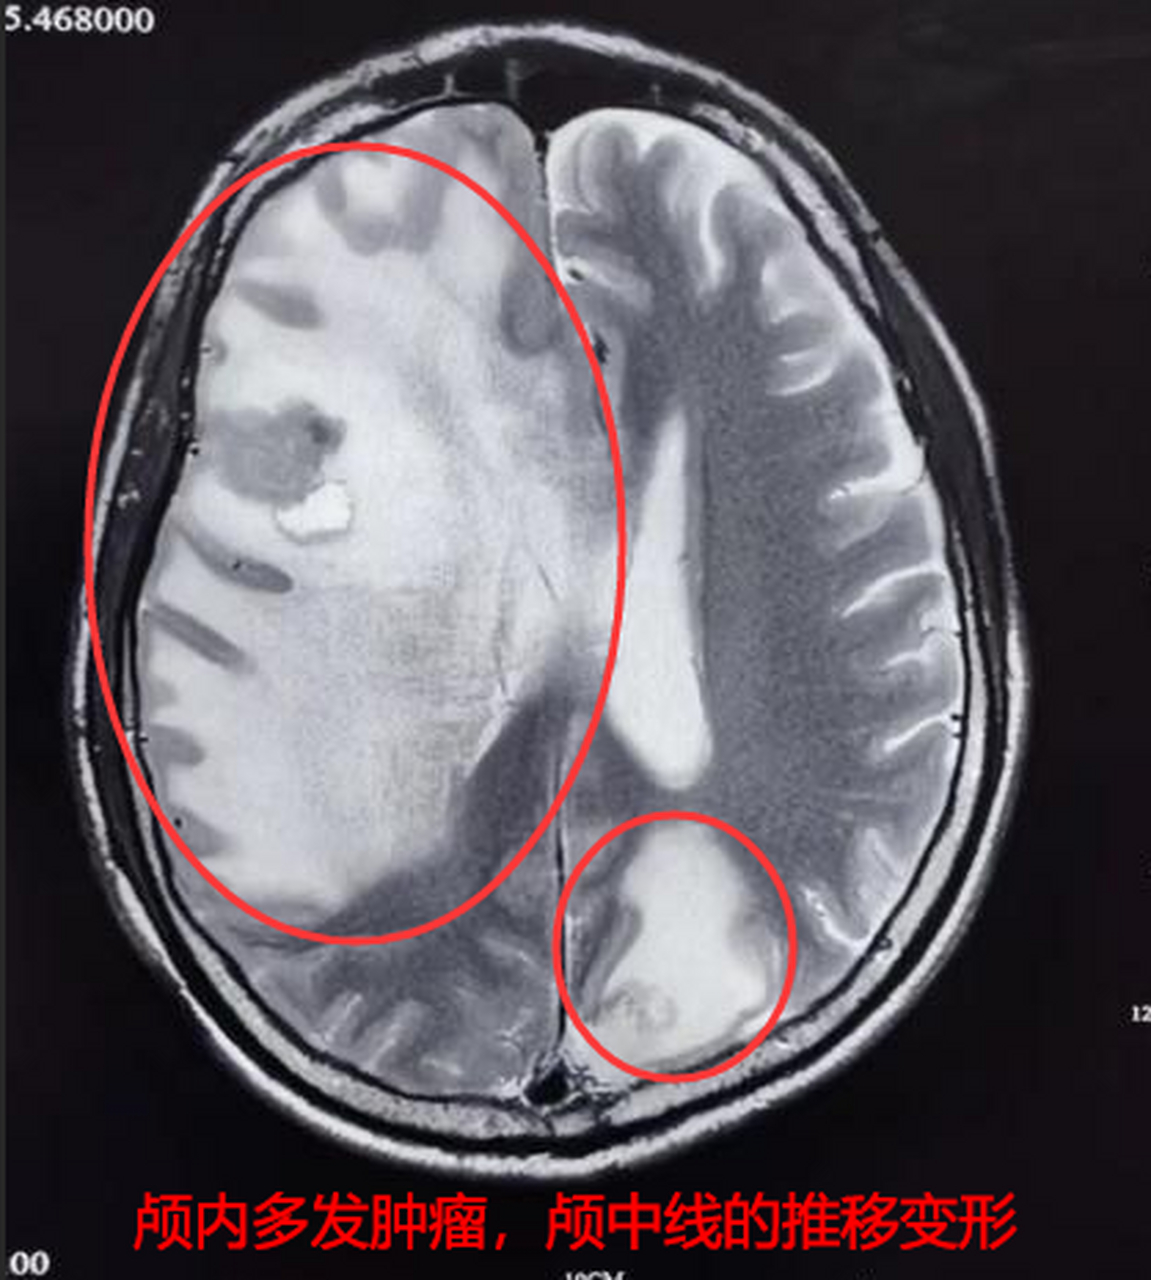

背景:62岁女性患者,2017年确诊晚期肺腺癌,经化疗、放疗及PD-1免疫治疗后,2021年出现脑转移(纵隔淋巴、右肺转移)。

7天后:头晕、头皮皮疹症状出现,但脑部核磁共振显示无进一步扩张。

3个月后:胸部CT和脑部CT复查显示肿瘤缩小(从2.45×2.15cm缩小至2.16×2.08cm),CEA正常。

8个月后:病灶总数减少23%,进入稳定阶段。

分析:印度奥希替尼对无基因突变的脑转移患者仍有效,且起效快,症状改善显著。